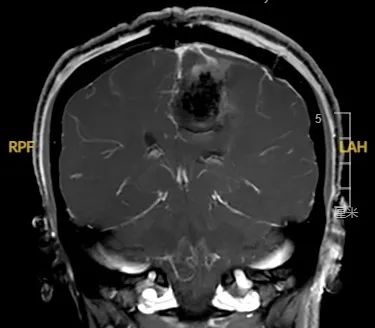

手术后

术后复查MRI,报告显示潘女士的脑膜瘤已完整切除。通过神经外科医护团队的精心照护,潘女士术后第7天已能下地活动,目前已康复出院 。术后复查核磁共振(MRI),报告显示潘女士的脑膜瘤已完整切除。